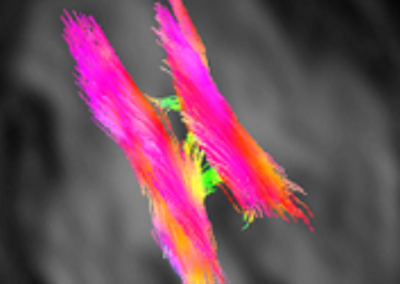

L’Université Paris Cité franchit une nouvelle étape dans le domaine de l’imagerie médicale anténatale avec l’acquisition d’un système d’Imagerie par Résonance Magnétique (IRM) 1,5T ARTIST™ de GE HealthCare. Cet équipement de pointe renforce les capacités de la Plateforme LUMIERE à l’hôpital Necker-Enfants malades, plateforme intégrée de soins, de recherche clinique et d’enseignement en imagerie médicale de la femme enceinte, du fœtus et du placenta.

Une avancée technologique majeure pour la recherche anténatale

L’inclusion de ces patientes, depuis leur accueil jusqu’à la réalisation des examens d’imagerie, puis l’analyse des images et l’interprétation des résultats par des équipes expertes, enrichit une base de données structurée, unique au monde, au service de la recherche et de l’innovation en imagerie anténatale et en médecine fœtale.